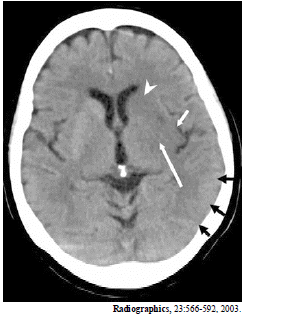

A imagem acima é de uma paciente de 65 anos de idade, com hemiplegia direita há cinco horas. Com base nessa imagem, é correto afirmar que

a cabeça de flexa indica o núcleo caudado.

A imagem acima é de uma paciente de 65 anos de idade, com hemiplegia direita há cinco horas. Com base nessa imagem, é correto afirmar que

as flechas negras indicam edema cortical no lobo occipital.